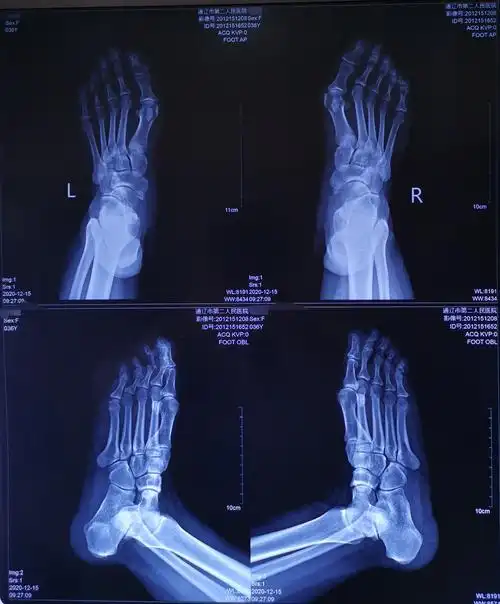

负重x线片观察:第一二跖骨间夹角增大明显,第二跖趾关节半脱位.

拇外翻的矫治